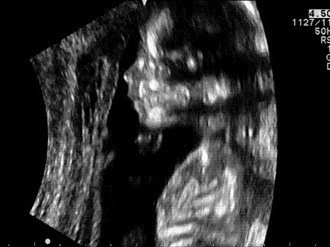

2. großes Ultraschall - Tagebücher aus der Schwangerschaft von Ophelia aus Köln